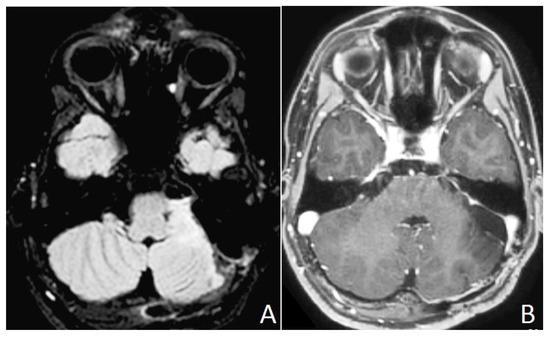

2. Case Presentation (Material)

2.2. Results